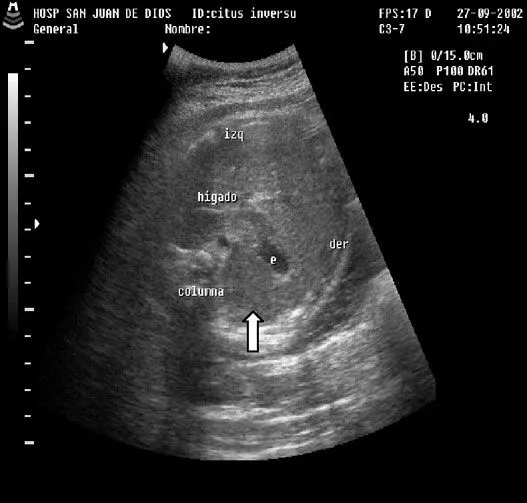

Revista chilena de obstetricia y ginecología - DIAGNOSTICO ...